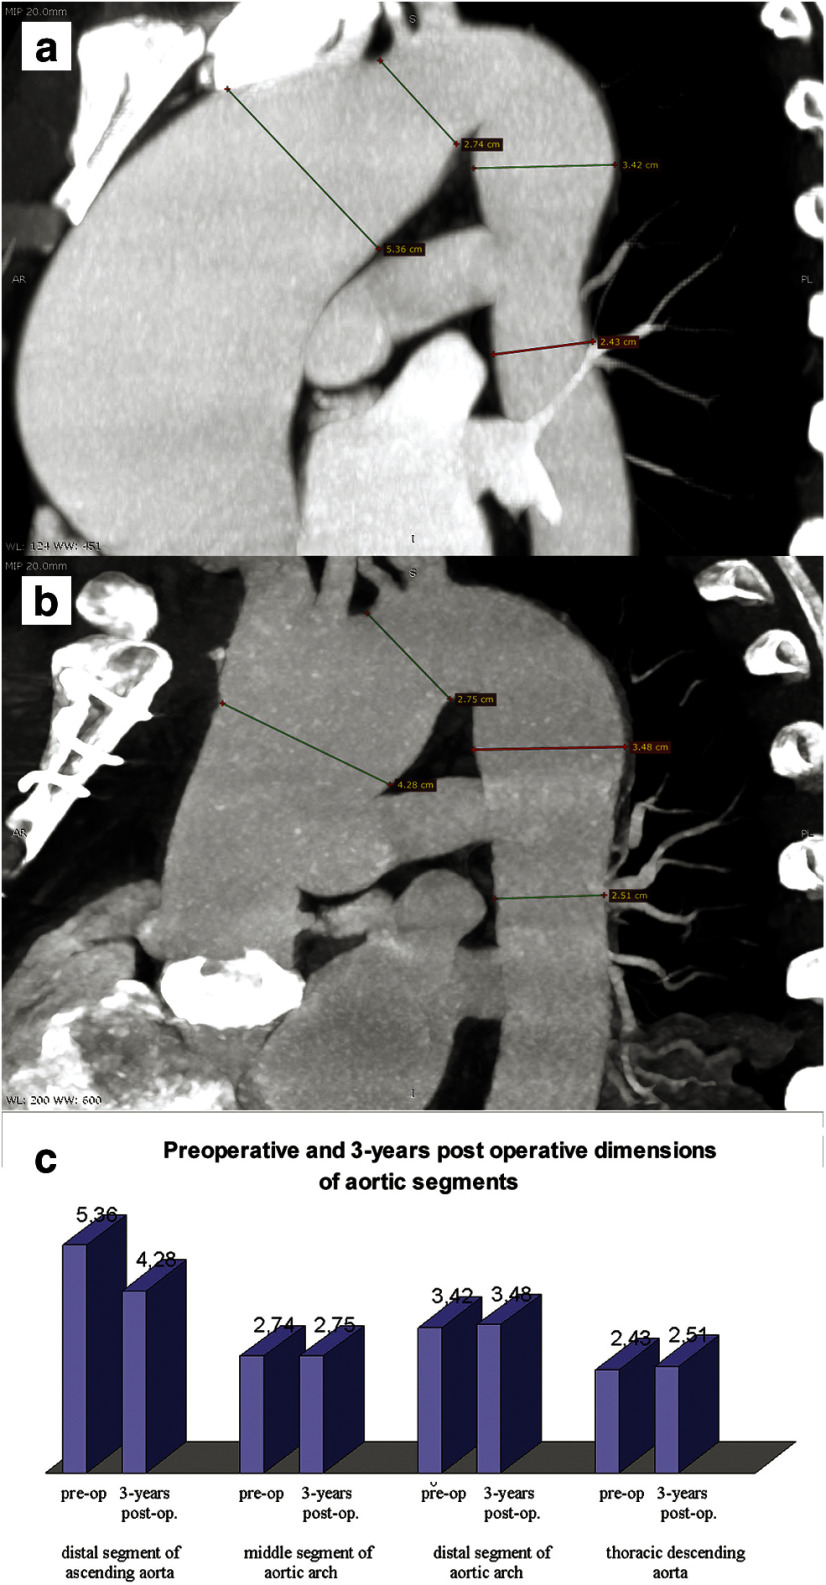

A syphilitic aortitis is a late cardiovascular lesion of tertiary syphilis that has become exceptionally rare in the antibiotic era but not eradicated completely. Syphilitic aortitis of ascending aorta complicates in ascending aortic aneurysm formation and aortic valve regurgitation, both requiring surgical treatment. After surgery, lifelong surveillance of the remainder of the aorta is recommended because of a priori supposed high incidence of delayed involvement of noninvolved aortic segments. A 3-year follow-up result of surgery of syphilitic ascending aortic aneurysm with aortic valve regurgitation in condition of active ongoing syphilitic aortitis and valvulitis is described with addressing the dimensions of remaining aortic segments. This case demonstrates that the dilatation of the remainder of the aorta does not occur during 3 years, at least when anti-syphilitic course of antibiotic is used just after operation without additional treatment during the follow-up period. A few reports on surgical treatment of syphilitic aneurysms of the ascending aorta are discussed.